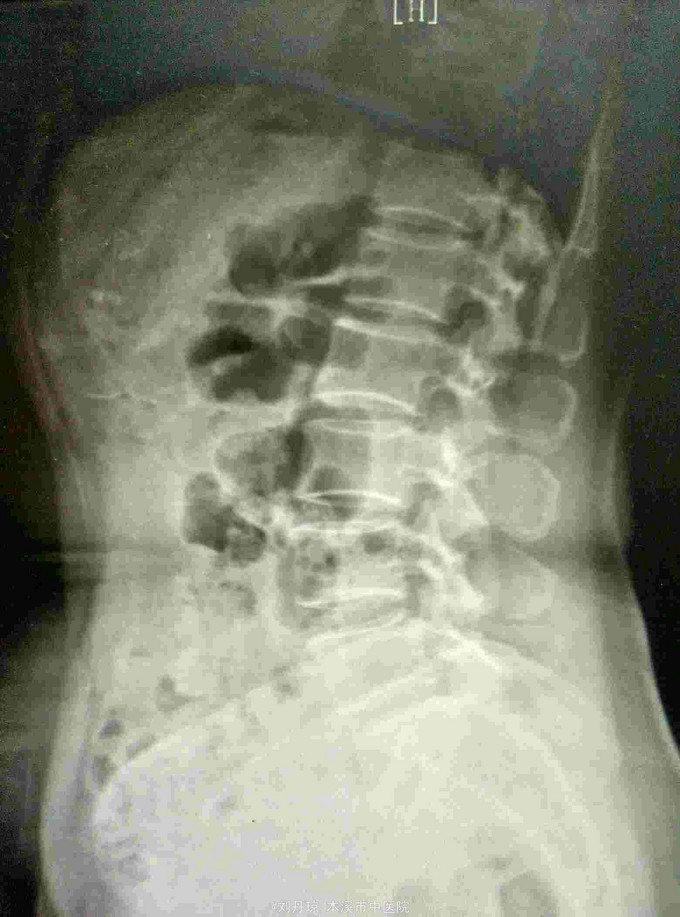

腰痛伴有右下肢放射痛三年,加重十天。患者三年前因抬重物腰部刺痛,休息一周后好转,十天前因开车劳累4.5小时后又洗澡,第2天即感右下肢放射痛难以忍受,遂由门诊收入院治疗。

查体:L5—S1棘突旁压痛阳性。直腿抬高实验。左70度,右30度。加强试验左侧阴性,右侧阳性。腰椎功能障碍。CT:L5—S1椎间盘突出。